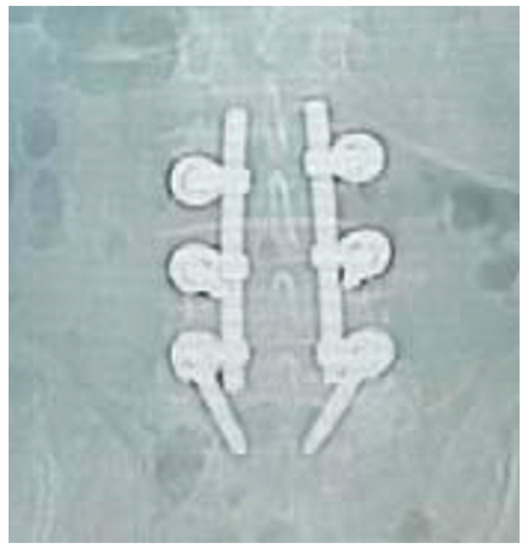

Figure 7. Post-operative coronal X-ray check—patient code: 2ATL3L4L5110.

Applsci 10 05977 g007

Figure 9. Post-operative coronal X-ray check—patient code: 5BML4L501.